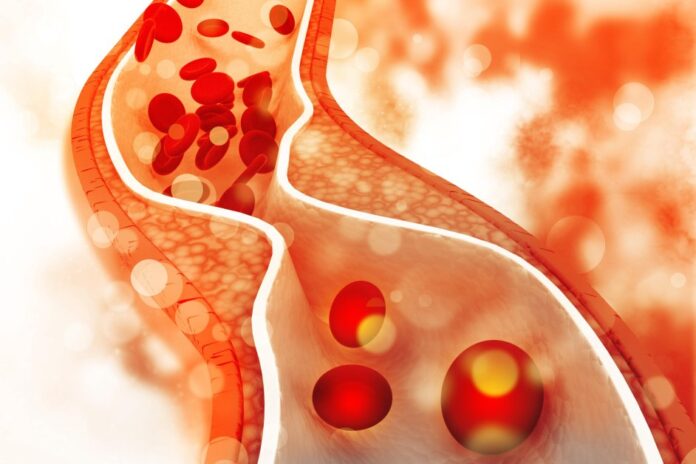

Натрупването на холестерол в тялото ви обикновено се дължи на диета, богата на мазнини, пушене, пиене, липса на упражнения или генетична предразположеност. Ако твърде много от този мастен холестерол започне да покрива кръвоносните ви съдове, това може да доведе до запушване, което да доведе до сериозни здравословни проблеми като инфаркти и инсулти.

Британската сърдечна фондация хвърли светлина върху ролята на холестерола, заявявайки: „Холестеролът е естествено мастно вещество в кръвта ви. Произвежда се в черния дроб и също така се намира в някои от храните, които ядем. Холестеролът е важен за поддържане на клетките в телата ни здрави.“

Те предупреждават: „Високият холестерол означава, че имате твърде много холестерол в кръвта си. Ако не предприемете стъпки за понижаване на високия холестерол, това може да увеличи риска от инфаркт и инсулт.“

Холестеролът не просто се носи наоколо; той пътува през обширната мрежа от кръвоносни съдове на тялото, често се натрупва в определени области с течение на времето. Една такава област може да бъде около очите, където могат да се появят три основни симптома.